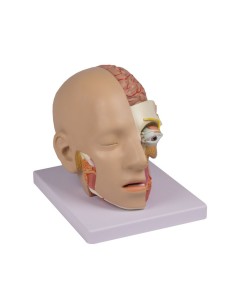

Scopri il Mondo dell’Anatomia con Modelli anatomici di Precisione

Dal cranio in 22 parti con incastri magnetici ai modelli di colonna vertebrale, da quelli di articolazioni a quelli di cuore, ogni pezzo della nostra collezione è progettato per un’immersione totale nello studio dell’anatomia umana. I nostri modelli, realizzati tramite scansioni di ossa vere, garantiscono un’esperienza tattile autentica e una fedeltà di peso quasi identica agli originali.

Essenziali per studenti e professionisti, i nostri modelli anatomici sono strumenti didattici che permettono di osservare le strutture anatomiche con precisione, eliminando la necessità di dissezioni o studi invasivi. Sono inoltre utili per spiegare ai pazienti le patologie, rendendo la comunicazione più efficace e risparmiando tempo prezioso.